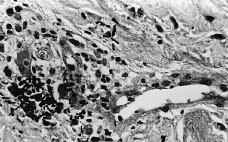

Se realizó biopsia cutánea para estudio histopatológico y cultivo. En 48 horas se recibieron los cultivos en sangre y piel con crecimiento de Trichosporon asahii, por lo que se añadió fluconazol al tratamiento. La paciente quedo afebril, pero se mantuvo la pancitopenia, con disnea y anuria, falleciendo 5 días después. El estudio histológico confirmó el tromboembolismo micótico que ocupaba la luz y pared vascular, que con la tinción de PAS ponía de manifiesto numerosas hifas y conidias (Figs. 3 y 4).

FIG. 3.--Presencia de abundantes hifas y esporas en zonas perivasculares de dermis media.